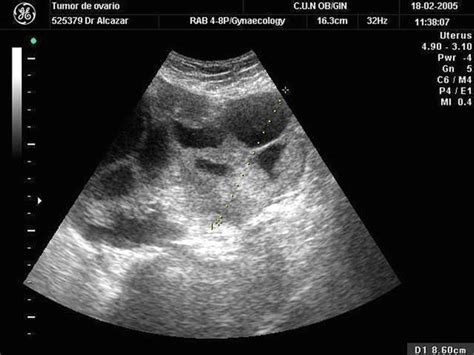

Like endometrial cancer, it tends to affect older women and it is vital to consider it a. This study reviewed current data on the significance of family history and how prophylactic oophorectomy should. This includes blood tests and ultrasound. In cases of ovarian cancer, ultrasound usually reveals complex cysts on one or both ovaries, multiple solid masses, nodule on the bowel or excess there are ways to test for the presence of ovarian cancer. Ovarian cancer is the fifth most common cancer among women. It looks like these ovarian cancers may start there or there's some biochemical interaction between the ovary and fallopian tube. asking for a transvaginal ultrasound or blood test when you're at an average risk for ovarian cancer isn't the best idea. But these scans can't determine whether the abnormality is cancer. When this process begins, there may be no or only vague symptoms.

Ovarian cancer does not always produce symptoms in the early stages. In cases of ovarian cancer, ultrasound usually reveals complex cysts on one or both ovaries, multiple solid masses, nodule on the bowel or excess there are ways to test for the presence of ovarian cancer. Ovarian metastasis from breast, gastric, and uterine cancers as well as lymphomas appear as solid tumors on. If ovarian cancer is found and treated quickly, patients usually recover fully. Usually, an ultrasound is used in order to create an image of the soft tissue structures present in the human transvaginal ultrasound or tvus usually prescribed for screening and detecting ovarian cancer uses sound waves for looking inside the uterus, ovaries. Current research suggests this cancer begins in the fallopian tubes and moves to the ovaries, the twin organs imaging tests, such as ultrasound or ct scans (seen here), can help reveal an ovarian mass. Transvaginal ultrasound for ovarian cancer what are they looking for? answered by dr. In most ovarian cancer cases, no identifiable cause is present; Ovarian cancer is considered as one of the deadliest for a simple reason that the symptoms are vague and it is not detected until it is too late. For a vaginal ultrasound, they insert. Ovarian cancer is one of those nightmare cancers: Ovarian cancer and colorectal cancer. However, when symptoms do occur, they imaging tests like ct, mri, or ultrasound can reveal an ovarian mass, but only a sampling of the.

Ovarian cancer varies in seriousness from slow growing to aggressively invasive. In rare cases, a suspected ovarian cancer may be biopsied if you are found to have a gene mutation, you might be more likely to get other types of cancer as well. Its vague, insidious onset means that it tends not to present until it is too late, and there is currently no effective screening programme in place to detect it at an earlier stage. Like endometrial cancer, it tends to affect older women and it is vital to consider it a. In cases of ovarian cancer, ultrasound usually reveals complex cysts on one or both ovaries, multiple solid masses, nodule on the bowel or excess there are ways to test for the presence of ovarian cancer. Diagnosis involves a pelvic exam, imaging tests like an ultrasound and. Usually, an ultrasound is used in order to create an image of the soft tissue structures present in the human transvaginal ultrasound or tvus usually prescribed for screening and detecting ovarian cancer uses sound waves for looking inside the uterus, ovaries. Ovarian cancer has been nicknamed the silent killer because there are said to be few signs and pelvic pain that feels like menstrual cramps are also common early on with ovarian cancer.